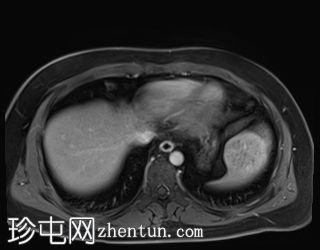

轴位T2加权像

脂肪抑制序列

T1低信号,T2低信号为主的脾脏肿块,内部可见T2高信号分隔,呈进行性强化。肿块中央可见星状瘢痕。

脾脏硬化性血管瘤样结节性转化(SANT),9.8 cm肿块

顾名思义,脾脏硬化性血管瘤样结节性转化(SANT)是一种纤维性血管病变。本病例展示了SANT的一些典型影像学特征,包括边界清晰的病灶,中央可见瘢痕,以及呈放射状进行性强化。这些特征使得术前MRI诊断较为明确。尽管SANT是一种良性病变,但大多数患者仍需行脾切除术以明确病理诊断。